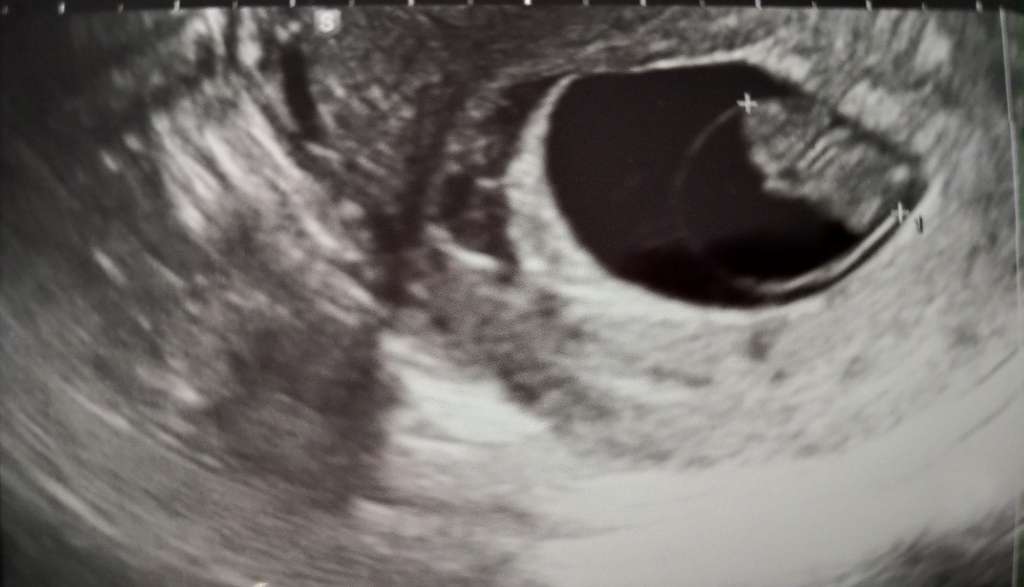

Jestem po wizycie. Wszystko dobrze. Jest maluszek z ogonem ;). Serducho bije.

• 0c08b1bb-30c5-466a-a34f-1eaa1e9d4bc1.jpeg

0c08b1bb-30c5-466a-a34f-1eaa1e9d4bc1.jpeg

34,3 KB · Wyświetleń: 95